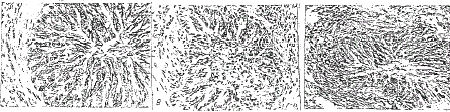

c-fos表达阳性细胞主要是支气管上皮细胞。哮喘组鼠上皮细胞浆染褐色的c-fos蛋白明显高于治疗组及对照组,见附图。

附图 细支气管C-fos免疫组化光镜病理改变(HE×40)片

A:正常对照组豚鼠,细支气管组织阳性蛋白表达不明显。 B:哮喘豚鼠:上皮细胞浆见较多染褐色的c-fos蛋白表达

C:DXM治疗豚鼠:上皮细胞浆可见少许c-fos阳性蛋白表达